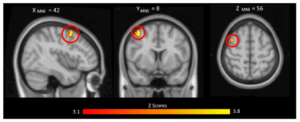

Parents activate brain regions linked with social cognition, reward processing, and emotion when viewing their own infant. Neural responses to own-infant stimuli may be driven by familiarity, self-relevance, or by the unique features of infant faces. The current study sought to clarify these distinctions in first-time fathers by contrasting video stimuli of their infant, an unfamiliar infant, and their pregnant partner.